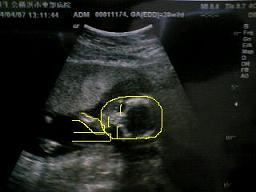

2007年4月4日撮影。

20w2d

BPD(児頭大横径)=5.03センチ

FTA(躯幹面積)=17.59平方センチ

FL(大腿骨長)=3.08センチ

推定体重=355.91グラム

左の写真はわかりにくいので右の写真で図解!